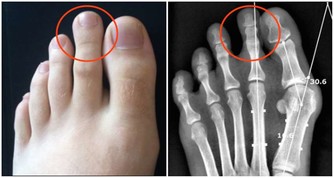

按照物質不滅定律,你使用降血糖藥之後你以為血糖下降了,你就錯了,血糖根本沒有消失,多餘的血糖就開始屯積在你的腳部,就好像糖積在杯底一樣,其結果就是雙足潰爛,你等著截肢吧!前台灣總統蔣經國先生就是受害者,如果你知道此案例,但是你卻沒有學到教訓,還是依樣的重導覆轍,你真是笨死的。

至於高血糖會持續多久,就要看你使用多少年的藥物控制,越多年自然越多的糖累積在雙腳內,而這些舊糖多年以來從未排出過體外,自然在吃中藥之後會迴流到身上,就會需要比較常的時間來消化它,每個人都不一樣的。